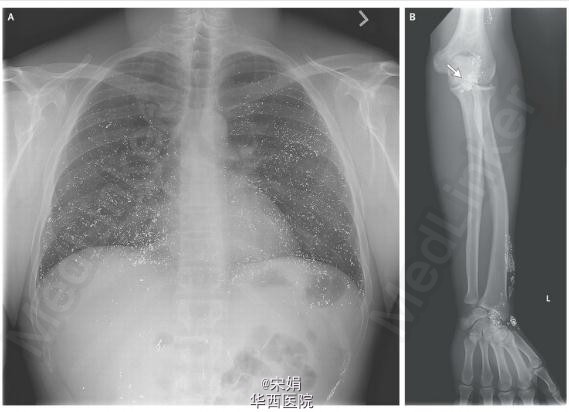

患者为男性,40岁。因头痛,干咳,呼吸困难3天而就诊。体格检查发现其情绪不稳,有意向性震颤,左前臂皮下有结节、触痛。患者此前经皮肤接触了液态汞,金属影的分布与浅静脉的走向一致,临床表现也与那些静脉和皮下自我注射汞患者的表现一致。在通过鼻导管吸入每分钟2升氧气的状态下,其血氧饱和度显示为92%。实验室检查显示其尿汞水平为1249微克/每升(正常参考范围,0~10微克/每升),而血汞水平则超过了160微克/每升(798 nmol/L;正常参考范围,0~10微克/每升,即,0~50 nmol/L)。该患者接受了2,3-二巯基丙磺酸钠(DMPS)螯合治疗。5天后症状缓解,复查其尿汞水平为692微克/每升。